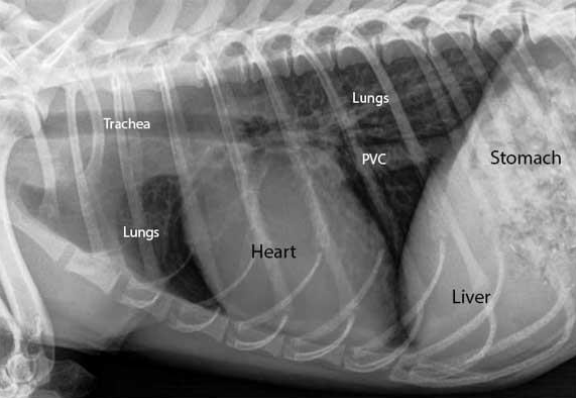

๐Ÿ”ท Thoracic radiography ํ•ด์„ํ•˜๊ธฐ

๊ฒ€์€์ƒ‰ ๋ฐฐ๊ฒฝ : ํํฌ (๊ณต๊ธฐ๋ฅผ ๋จธ๊ธˆ์–ด์„œ)

๊ฑฐ๋ฏธ์ค„์ฒ˜๋Ÿผ ์ด์–ด์ง„ ๊ฒƒ : interstitium (๊ฐ„์งˆ)

V : ํ˜ˆ๊ด€

๊ฒ€์€ ์ค„ : ๊ธฐ๊ด€์ง€